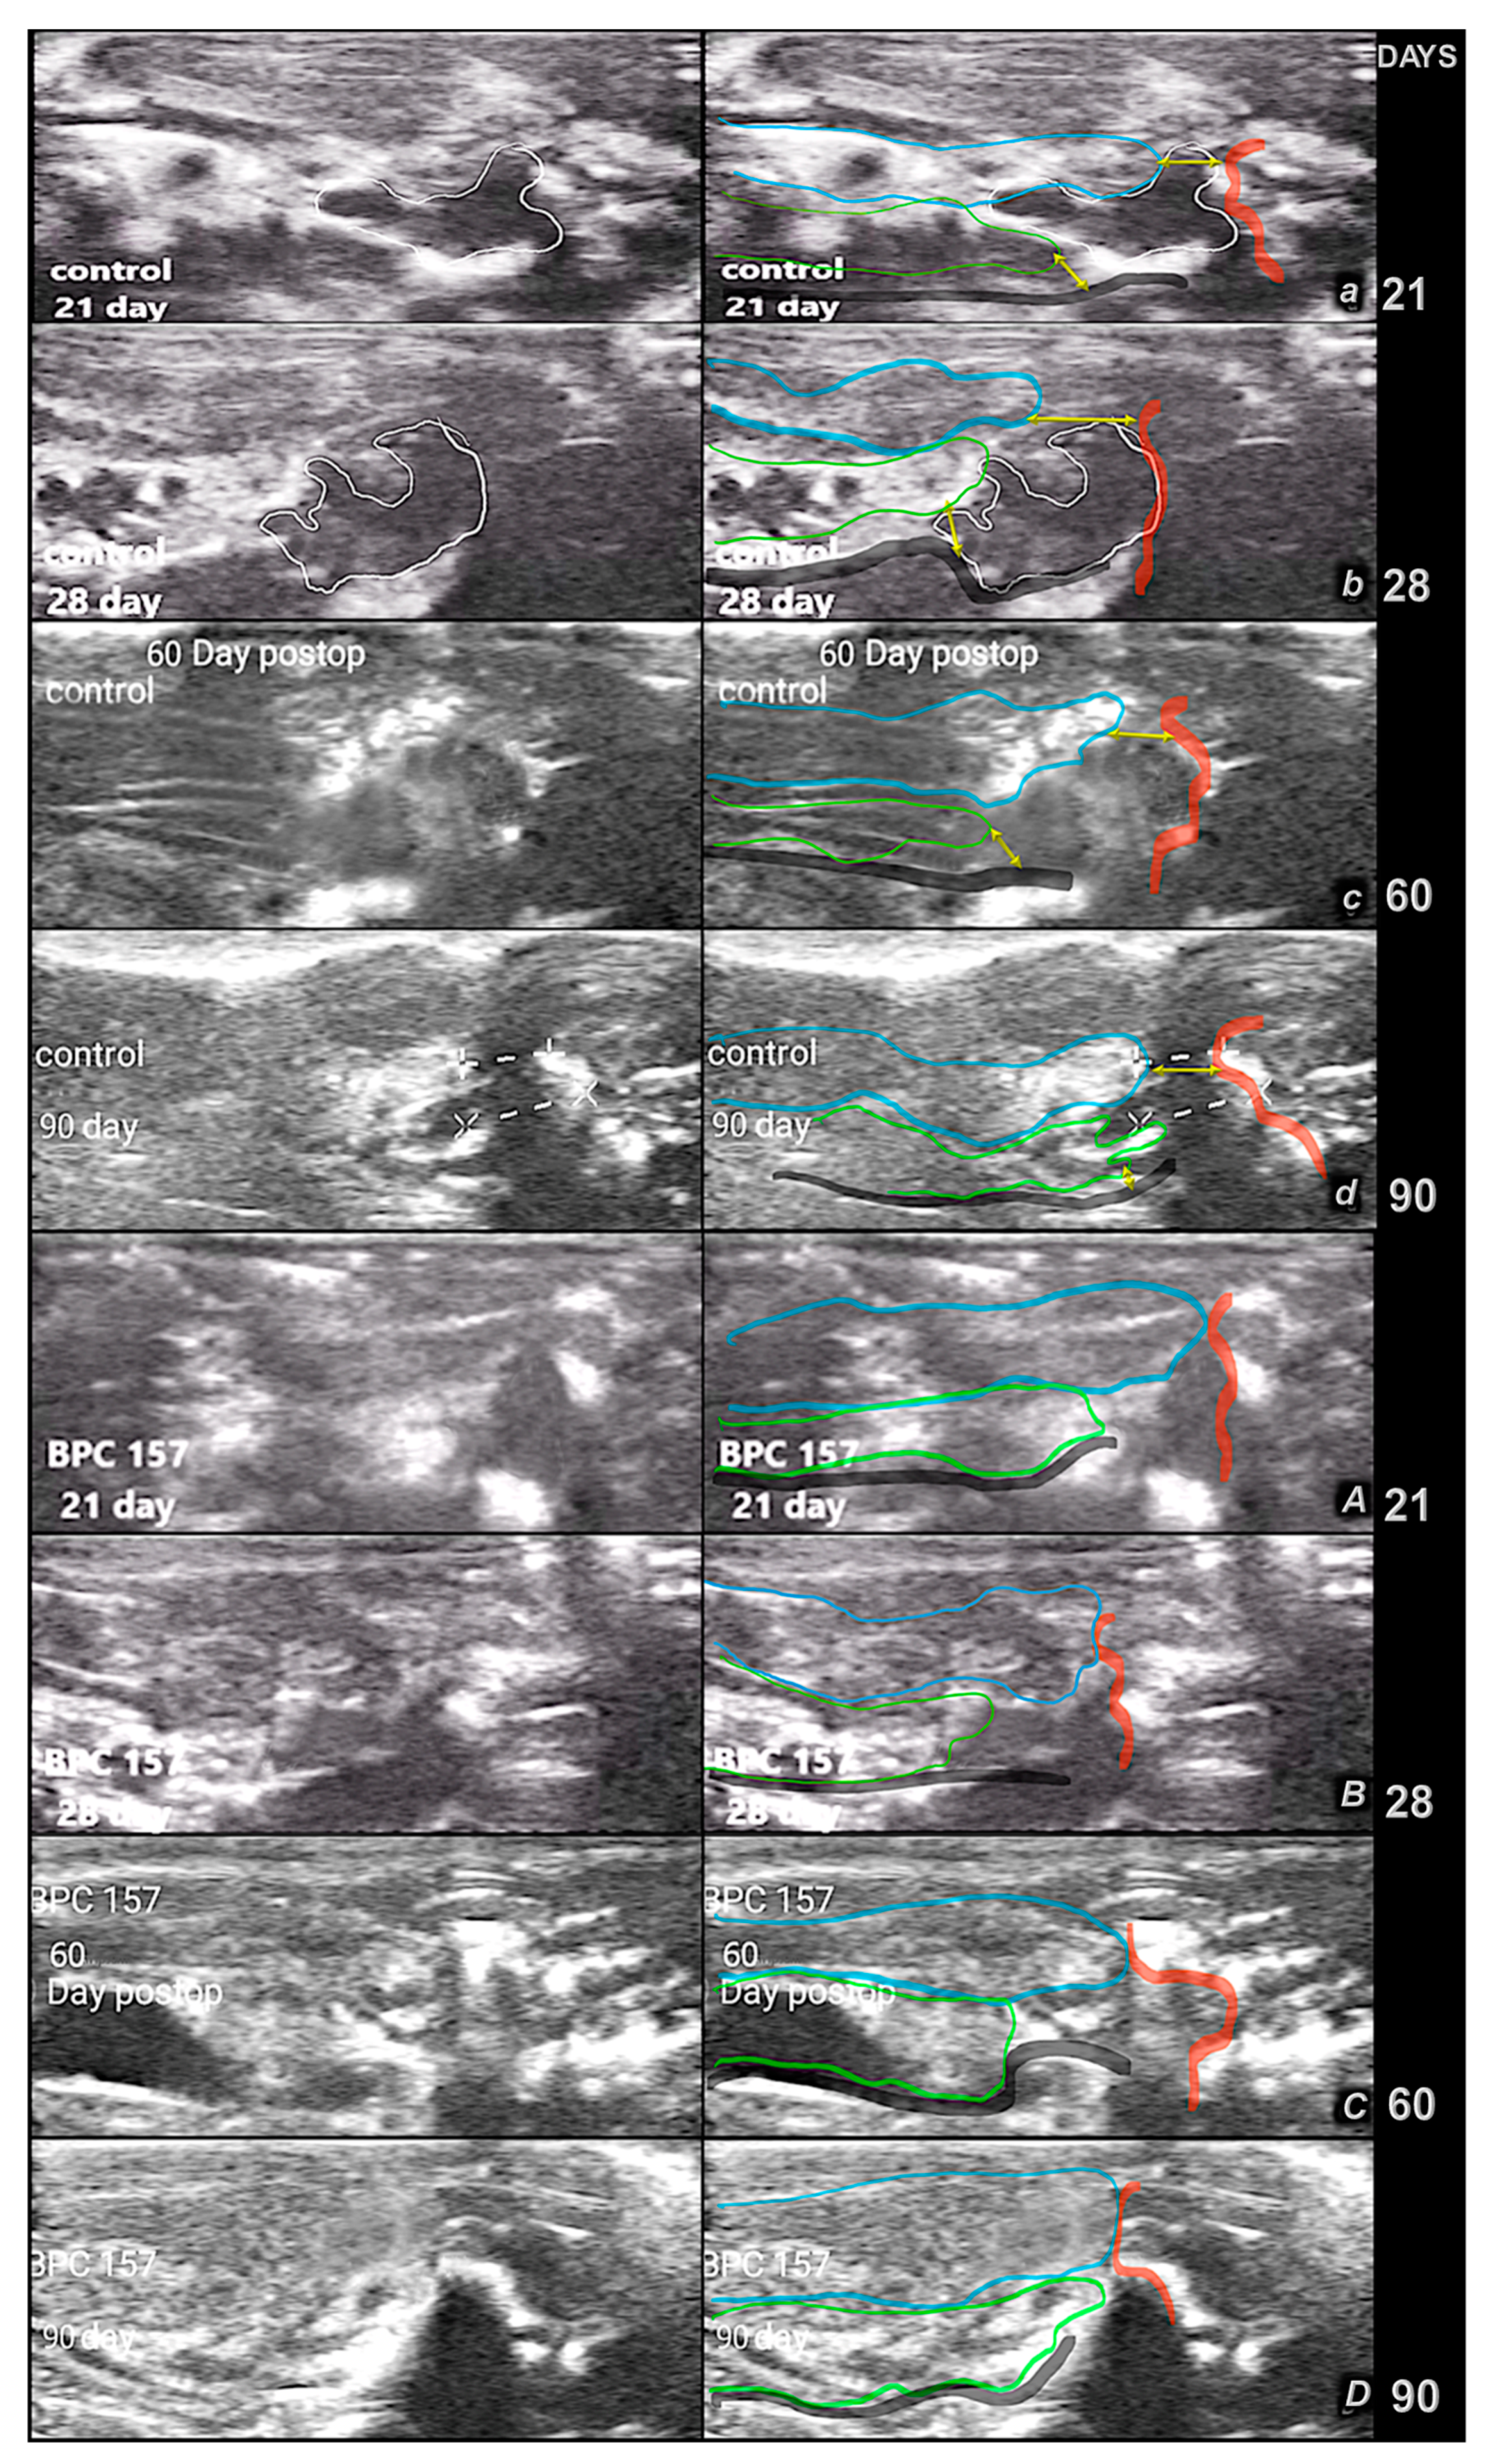

2.5.4. Ultrasonic Imaging and Measurements

2.5.5. MRI Imaging and Measurements